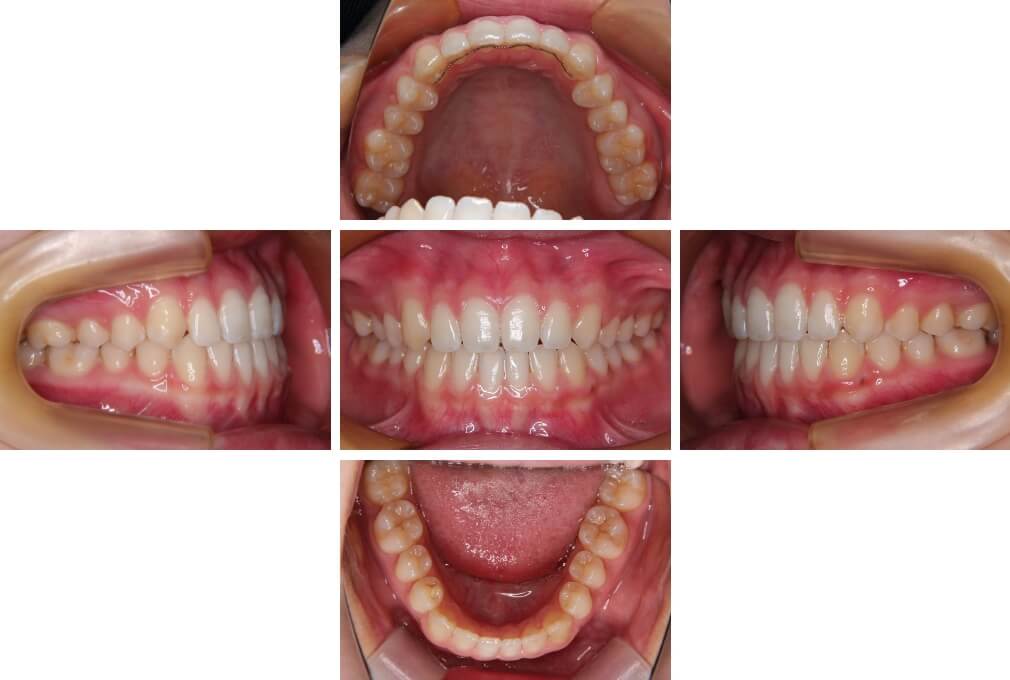

CASE:03

上下顎前突

初診時年齢 18歳4か月

性別 男性

治療費の目安 105万円程度(治療開始時)

歯列の乱れは著しくなく上顎右側側切歯が捻転し口蓋側へ転位していた。また、問診の中で患者さんから最も重視する治療結果として口元の突出の改善の申出があった。下顎が後退した上顎前突傾向ではあったが著しいものではなかった。上下顎前突と診断し上下顎小臼歯抜歯を行っていただき、上下顎舌側マルチブラケット装置を使用して、矯正用アンカースクリューを併用して動的治療を行った。上下顎前歯の後退を十分行い口元の突出感も改善した。治療後10年1か月の来院時には口元の突出感が再発することもなく、下顎前歯の少しの唇舌的なずれはあったが歯列は安定していた。動的治療期間2年2ヵ月間。

治療前

18歳4ヵ月

治療後

動的治療期間2年2カ月間

20歳10か月

10年経過

動的治療終了後10年1カ月

30歳11か月